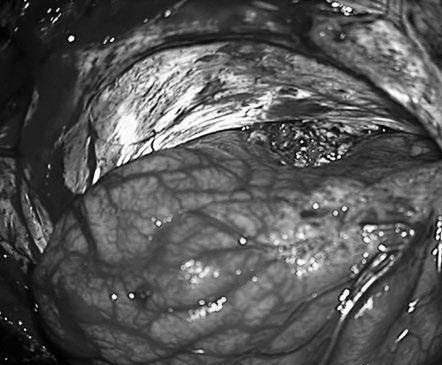

患者案例1:该患者为47岁男性,表现为合并胼胝体AVM的较大胼周动脉瘤破裂后昏迷(补充Spetzler-Martin分级为6级:S2V1E0/A3B0C0)。

手术步骤图解

他紧急行半侧颅骨切除术,随后血管造影显示右侧动脉瘤,AVM由双侧PcaA供血,引流向前MedFrV和SplenV【左侧ICA像,(a)前后位(b)侧位】(c)首先通过双侧开颅并排夹闭动脉瘤(鼻朝右,中线呈水平,重力牵开右侧额叶),然后切开动脉瘤使之缩小。